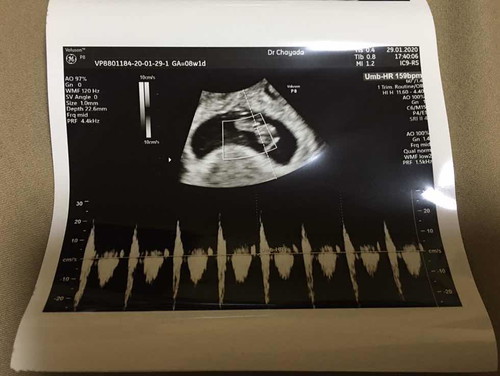

เห็นหลายๆเคสเลือดออก แต่แม่ๆก็ยังไม่รีบไปหาหมอเห็นแล้วก็อดเป็นห่วงไม่ได้ว่าทำไมไม่รีบไปหาหมอก่อน ประสบการณ์เราเองจะช่วยแก้ปัญหาทุกอย่าง ตัวเราเองก็เลือดออก แต่เลือดไม่ได้สดไม่ได้แดง เรายังกลัวลูกจะหลุดเลยโดนแอดมิดไป 1 คืน วันที่ 2 จะแอดมิดอีกแต่หมอก็บอกสาเหตุไม่ได้ ตัดสินใจเข้าเมืองไปตรวจกับหมอสูติดีกว่า ซาวด์ผ่านช่องคลอด ผลออกมาน้องยังปลอดภัย แข็งแรง เกาะแน่นมาก หัวใจเต้นปกติ 159ครั้งต่อนาที ในอายุครรภ์ 8วีค1วัน โชคดีเลือดที่ออกอยู่คนละฝั่งกับที่ลูกเกาะ หมอก็บอกไม่ได้ว่าเลือดออกเพราะอะไรแต่เลือดจะหยุดไหลไปเอง